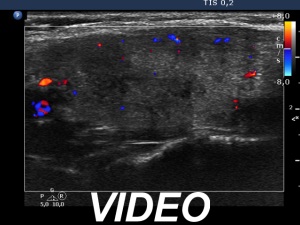

Two years after the first visit (second row of images):

Clinical presentation: The patient requested evaluation of neck complaints. Her left thyroid became painful and she became feverish 3 weeks ago. She suffered from upper airways infection 2.5 months before the onset of complaints.

Palpation: Both lobes became hard. The right lobe was very sensitive while the left was painful on palpation.

Laboratory tests: TSH 0.02 mIU/L, FT4 30.7 pM/L, CRP 51.8 mg/L.

Ultrasonography: The thyroid became minimally hypoechoic and more hypoechoic areas have appeared in both lobes. The echogenicity index was 20% and 50%, right and left lobe, respectively. The vascularity was decreased.

Suggestion. Steroid therapy.